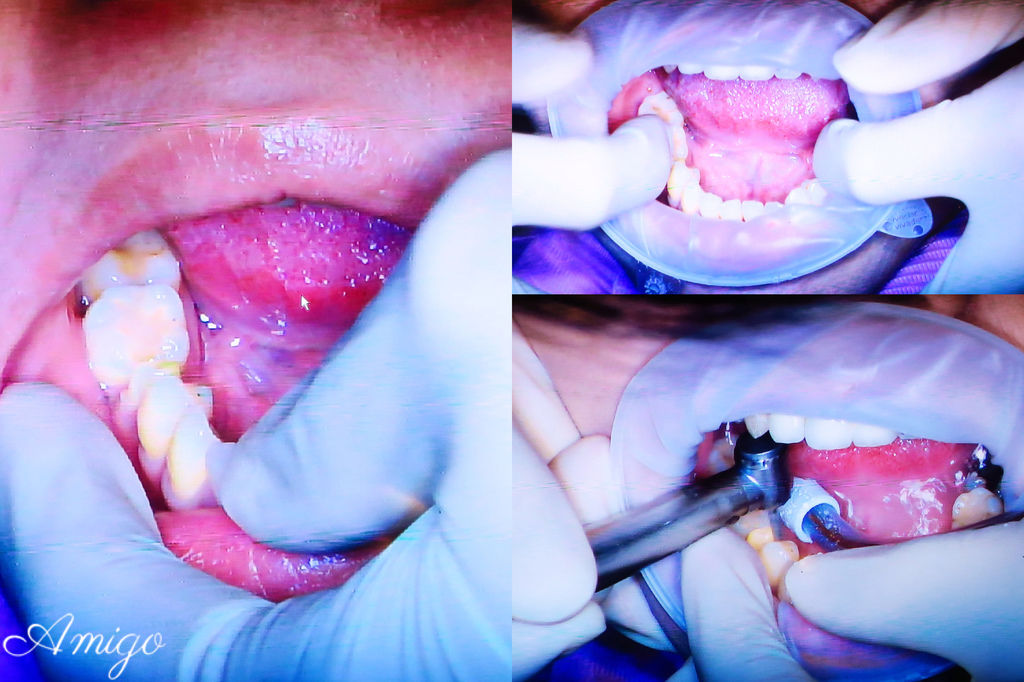

本次病患做假牙的部位是畫面左邊倒數第三顆的小臼齒

曹醫師先將真牙磨成適合放置牙套的大小

接著

技師透過德國VITA比色儀 來比對前面一顆牙齒的顏色

機器上立刻顯示出與牙齒接近的瓷塊色號

再以牙齒的比色板 放在牙齒旁邊做實際上的顏色確認

與醫師討論出確定出要做的全瓷冠牙套

接著使用德國先進的全口3D全彩取像儀 來掃描口腔內的狀況

這個動作取代了傳統在患者口內做石膏灌模的程序

只需要張開嘴巴 不必侵入牙齒就能完成電子掃描

醫師將假牙套放入患者口腔中比對

確認準確度無誤後

再進行標準的消毒清潔的程序

以氫氟酸將全瓷假牙內部進行消毒

之後再沖洗乾淨▼▼▼

口腔內則使用PH值0.5的檸檬酸消毒後沖淨▼▼▼

再次套上牙套後 以專用黏著劑永久黏著

透過取像儀檢視

邊緣的密合度高 加上逼真的全瓷牙冠

幾乎分不出來哪一顆是假牙

最後用光療固定黏著劑

再以色紙確認牙齒的咬合狀況沒有問題

患者便可以開開心心回家~